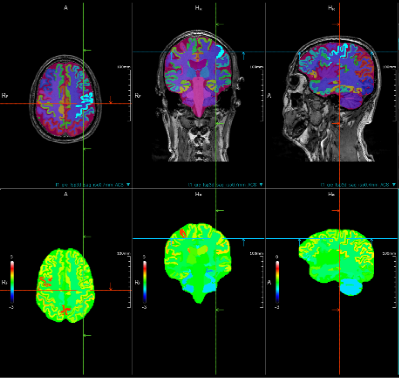

对于脑功能图像及数据处理,可支持神经结构图像处理、神经功能数据分析。

大脑结构 大脑血管及神经纤维束